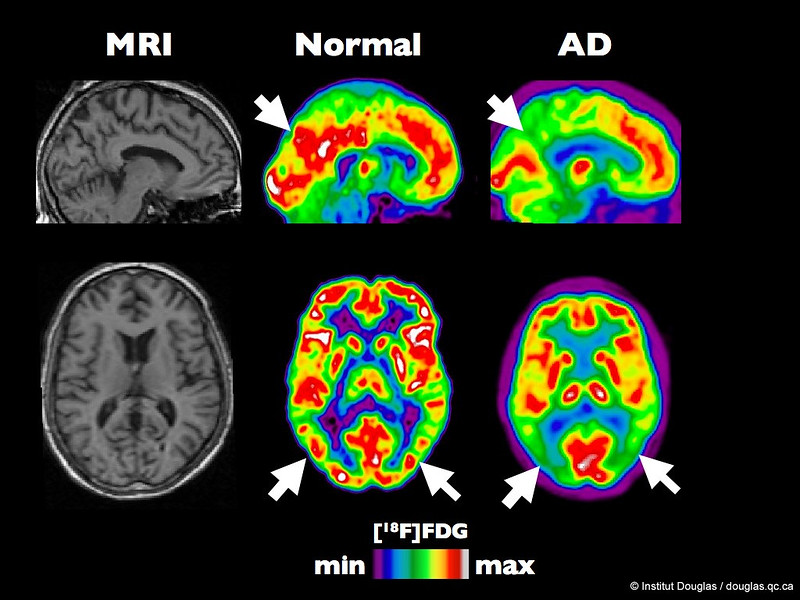

A Loss of Proper Brain Blood Flow

Blood carries essential components to the brain, like oxygen and sugar (glucose), providing energy to support brain activity. Brain blood flow decreases normally with age, and even more with Alzheimer’s. The decline seen in Alzheimer’s can significantly impact brain activity—making even the most basic cell functions difficult. This can have wide-ranging implications for cells and overall brain health and likely contributes to cognitive decline.

Alzheimer’s Disease Research grantee Dr. Marta Casquero-Veiga is developing new imaging tools to identify small brain blood clots that develop in Alzheimer’s. Learn more.

Running Low on Brain Fuel